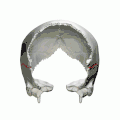

Parietal bones (above) and temporal bones (below). -